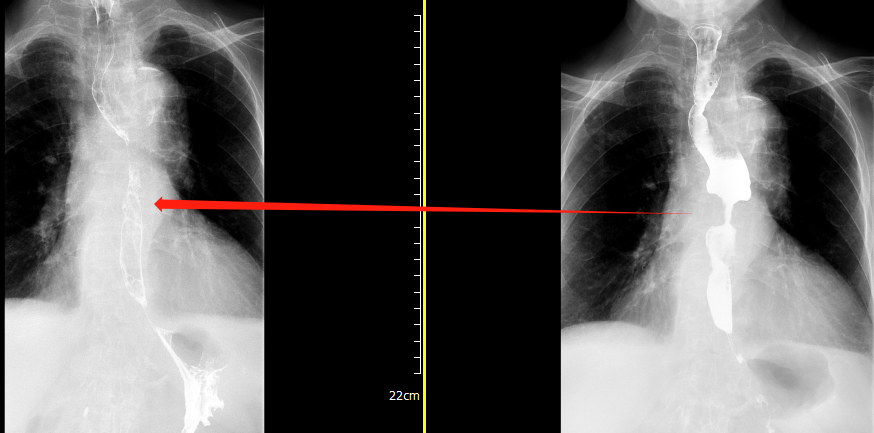

洪阿婆經(jīng)數(shù)次放療后即可半流質(zhì)飲食,從入院時的嘔吐到可進食稀飯還不到半個月。至今共放療15次,復(fù)查食管造影提示中段腫瘤部位明顯退縮,放療效果立竿見影。

▲放療前與放療15次后的食管造影對比